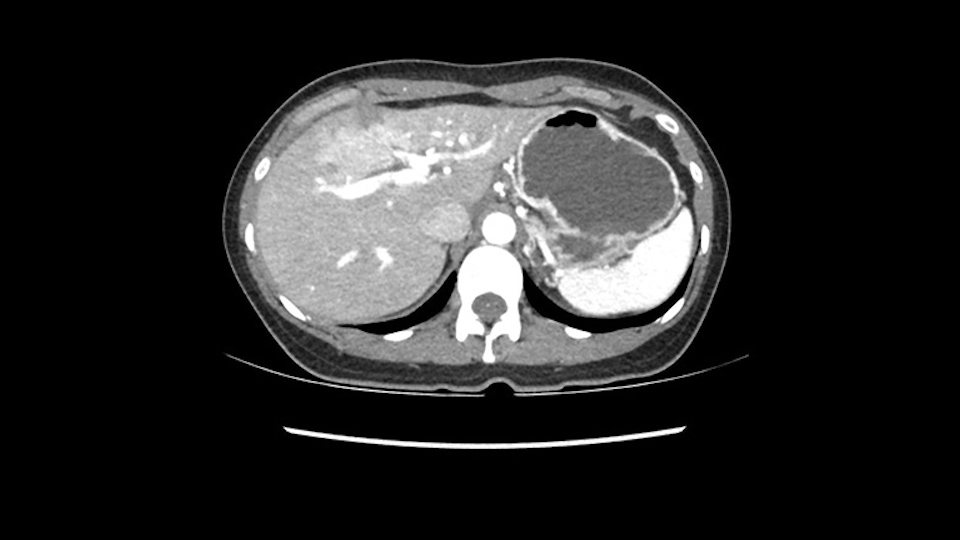

So if we look at the CT scan, on the axial, it’s a larger lesion. It’s about 6 or 7 or 8 centimeters. So it does look a bit threatening in terms of its resectability but if you really drill down deeply into the anatomy, and I think the coronal [imaging] is even better, you can see that the entire mass is on the patient’s left side of the falciform ligament. So it’s really only a left-sided tumor and not even really a left-sided tumor because Segment 4 is uninvolved anatomically.

As I review the CT scan, we have both arterial and venous phases, the tumor is obvious. But I’ll start by saying that the liver itself does not appear to be cirrhotic to my eye. It’s got a normal contour and allied to that, that I do not see evidence of portal hypertension. The spleen is normal, there’s no collateral vessels. The tumor itself, I measured maximally at about 11 centimetres in diameter and I’m told the alpha fetoprotein is very high (over 10000), which is entirely consistent with this being a solitary hepatocellular carcinoma that is very exophytic. It seems to emanate off the inferior margin of Segment 3 (because that’s the falciform). I’ll start by saying that this is not transplantable. The tumor exceeds our guidelines for transplantation, but it's likely resectable based on normal liver and no portal hypertension.

When you see the axial sections of the scan, you find it's a largely exophytic mass and its well-encapsulated. So this is typically true of a well-differentiated hepatocellular carcinoma. If you look at this, this is the gallbladder which is being displaced to the right and the mass is in the Sg4 of the liver, exophytic, projecting down. As it is coming down, it is also displacing the duodenum and the head of the pancreas which is being pushed towards the left and it's going right up to the cava, the start of the anterior surface of the cava. Obviously getting a lot of collaterals and vascularity from all the vessels around but one has to be very careful in evaluation of the main portal pedicle in this particular case and of course arterial inflow to the Sg4 and of course the left lobe of the liver.

So in planning for this operation, as I look at the scans, I first visualize the arterial phase and I can see that there’s are a lot of big feeding arteries to this large tumor. Likely all the right side vessels feeding the right side of the liver: right hepatic artery and likely the Segment 4 artery are spared from the tumor. It’s likely the left hepatic artery is ramificating and giving feeding arteries to this tumor. It certainly looks like a large mass that its compressing other structures like the cava, the pancreas, the stomach; but I think there’s a plane and we can see that better in the venous phase. There’s a plane of separation between the gallbladder, the pancreas, the cava, that this tumor is abrupting but likely not invading. Usually, these masses actually don’t invade at that level and basically are pushing the tissues and once you open, you’re able to separate the tumor. Sometimes there’s some adhesions but you can actually separate and there’s usually no invasion.